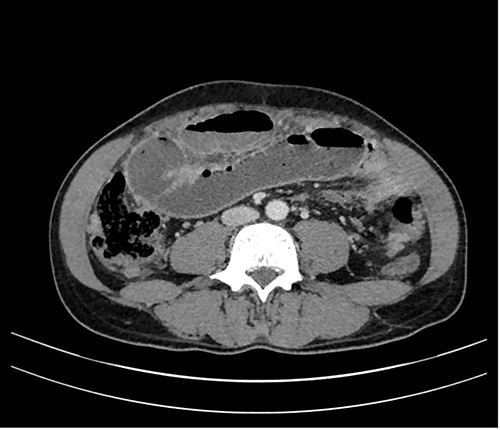

In a previous healthy 41-year-old male with a 3-month history of abdominal pain, fever, fatigue, night sweats and weight loss of 5 kg, a computed tomography (CT) of the abdomen revealed a mechanical ileus due to suspected distinct peritoneal carcinomatosis in the entire abdomen of an unknown primary (Fig. 1).

On palpation, there was a tenderness in the entire abdomen. Notable laboratory findings were: hemoglobin of 122 g/l (135–172 g/l), serum amylase of 61 U/l (13–53 U/l) and c-reactive protein of 62.2 mg/l (<3.0 mg/l). After conservative therapy with a nasogastric tube, intravenous fluids and laxatives failed, we went for diagnostic laparoscopy.